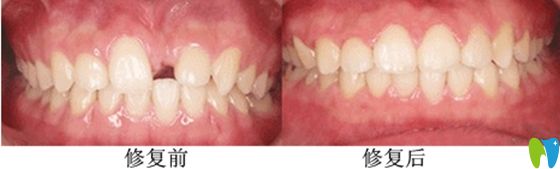

(德正口腔采用瑞士ITI種植系統(tǒng)修復(fù)的門牙缺失效果圖)

鄭州德正口腔前牙美學(xué)種植前后效果對(duì)比圖